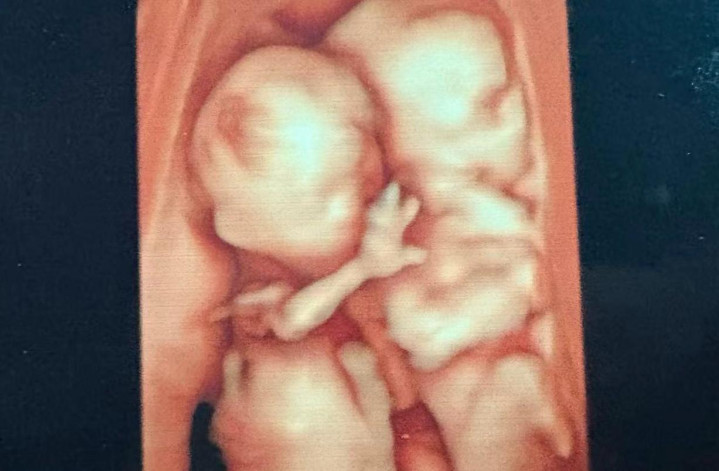

正巧的是,在产妇谭女士发来的相片里,宝宝抬起的手势也和孕12周作念NT时拍下的小手一模相同。

据了解,这是一双曾被会诊为双胞胎输血详尽征的宝宝。

本年7月,谭女士因孕期腹胀来到湖南省妇幼保健院看诊。B超潜入两个宝宝发育情况远隔等,一个宝宝真是莫得羊水,膀胱不潜入,被羊膜分隔瑟索在边缘里活动遏止;另一个宝宝的羊水却多得惊东谈主,像个洪水球。“正因为短时期内羊水彰着增加,导致谭女士出现了腹胀症状,这便是典型的双胎输血详尽征TTTSII期的施展。”苏慧琳说。

苏慧琳先容,双胞胎共用一个胎盘,两个宝宝应当是血液重复保捏均衡的,当均衡被突破之后,就会出现一个宝宝向另一个宝宝捏续输血的情况。经查,谭女士腹中的小宝(供血儿)像个小水泵,通过胎盘名义的血管温和之滚滚不断地把我方的血液“泵”给了大宝(受血儿),导致小宝得不到富饶的血液和养分,出现羊水少,发育迟缓,而大宝因接管太多的血液,羊水过多,腹黑超负荷职责心衰,导致两个宝宝皆堕入危境境地。如若不足时骚动,两个宝宝皆可能保不住。